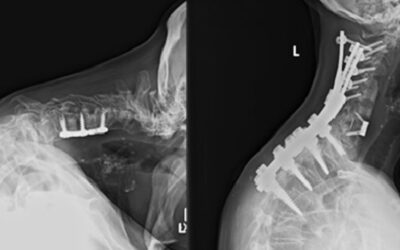

2. Surgical Intervention: For moderate to severe cases, surgery may be necessary to relieve pressure on the spinal cord. Common surgical procedures include decompression, laminectomy, or spinal fusion.

Diagnosing cervical myelopathy involves a combination of clinical examination and imaging studies. A healthcare provider will assess neurological function through tests that evaluate reflexes, muscle strength, and coordination. Imaging studies like MRI and CT scans are crucial for visualizing the extent of spinal cord compression.